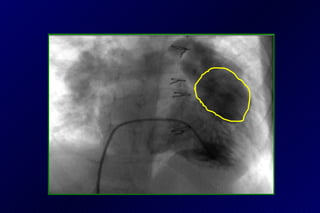

Tetralogía de Fallot operado

Tetralogía de Fallot

Tetralogía de Fallot: 46a

29a de postop ERPI

Angioplastia con stent

PRE                          POST

VD/Ao: 0,7                    VD/Ao: 0,43